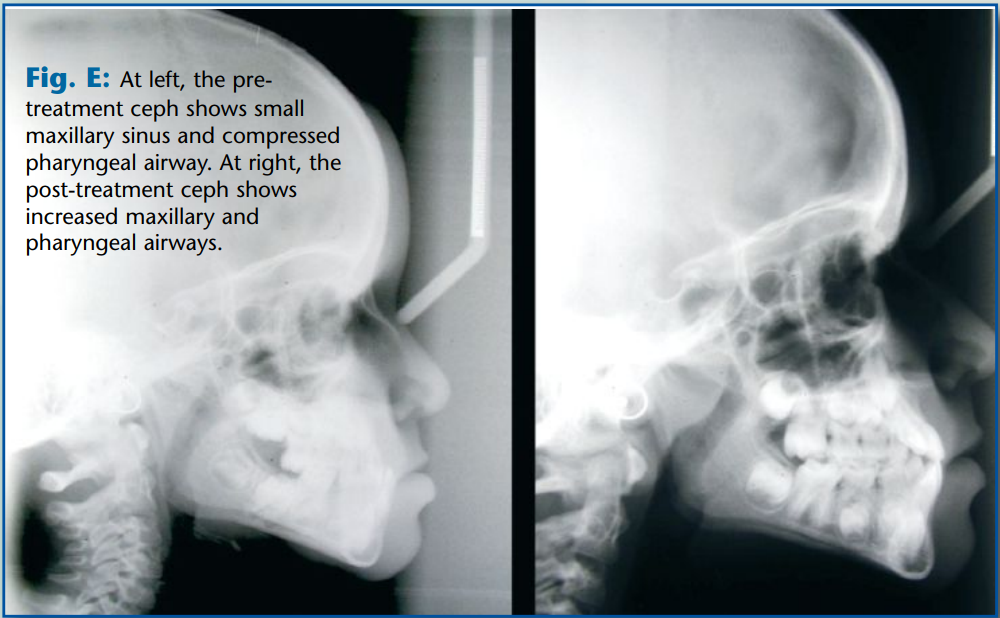

Note that the patient’s pre-treatment facial disharmony was caused by an underdevel- oped maxilla and protrusive mandible. Her underdeveloped maxilla caused her maxillary sinus to be compressed anterior-posteriorly. The Frankel III appliance developed her maxilla and, in turn, enlarged her maxillary sinuses, increasing her capacity to breathe nasally. Additionally, her pharyngeal airway increased after treatment. Fig. E shows the patient’s narrow A-P maxillary sinus radiographically before treatment, as well as her narrow pharyngeal airway.

Her post treatment ceph clearly shows that both her maxillary sinuses and pharyngeal airways enlarged to allow more efficient respiration, critical for her total health and wellness.